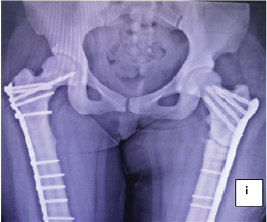

Complications of Limb Salvage in Concordant Bilateral Fibular Hemimelia and Tetramelic Ectrodactyly: A Case Report

Mark A Bachir , Iyawnna J Hazzard , Alexander S Bachir , Simran K Gill , Gavin S Chima , Biljinder S Chima

………………………………p.273-278